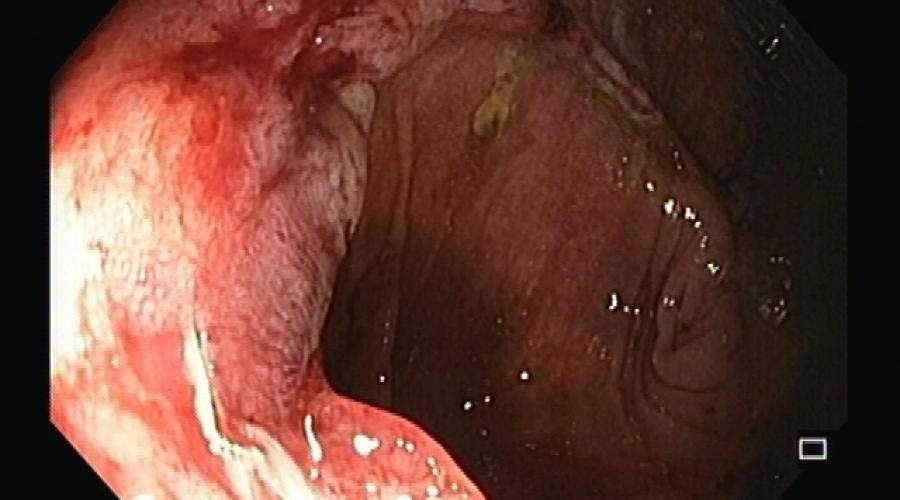

Obstrução do trato de saída gástrico

Observe em um minuto o algoritmo de atuação proposto.Aprofunde conhecimento ou reveja mais globalmente este tema nos artigos...